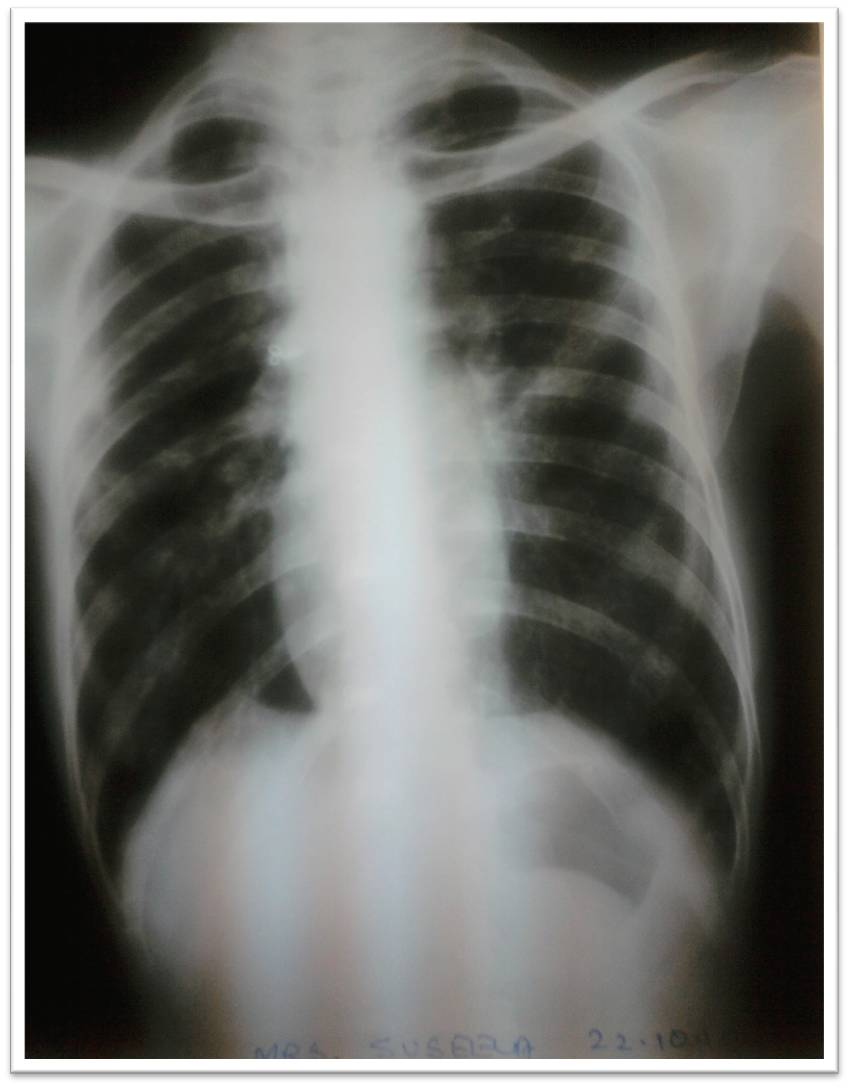

LBBB in DCM

Here is an ECG of a patient who came to our OPD absolutely asymptomatic for a routine review . He is been diagnosed as a case of dilated cardiomyopathy with 30% EF and no evidence of ongoing ischemia.If the history is not known he would have been diagnosed as a ACS.